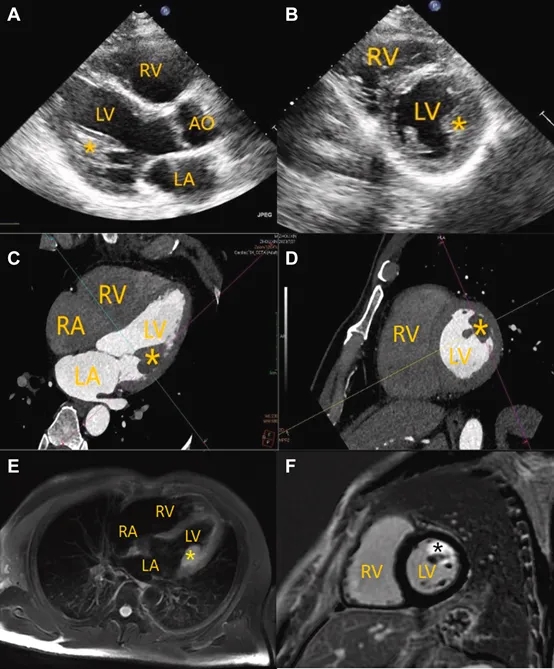

超声心动图显示,在左心室中侧壁邻近前乳头肌处,有一大小约27.5×16.5mm的中等回声团块,与邻近结构分界不清(图1A、1B,动图1、2)。通过胸骨旁长轴、改良胸骨旁短轴及心尖四腔心切面进行彩色多普勒检查,未探测到明确的瘤内血流信号,考虑血流信号的缺失很可能源于声学局限性。

图1多模态影像学检查结果

(A、B)经胸超声心动图显示左心室侧壁邻近前外侧乳头肌处存在一边界不清的团块;(C、D)计算机断层扫描显示乳头肌附近一边缘不规则的低密度病灶,部分与腱索结构融合;(E)心脏磁共振成像(T2加权压脂序列)显示团块内部呈均匀高信号;(F)延迟期心脏磁共振成像可见明显的“云絮状”强化表现;(图中)星号标示团块位置。

超声造影显示团块内部灌注程度较邻近心肌组织轻度减低。CT平扫可见一低密度病灶(CT值:54 HU),形态欠规则,部分与腱索结构相融合(图1C、1D)。心脏磁共振成像于左心室游离壁旁见一大小约33×19×20mm的团块,T2加权压脂序列上呈均匀高信号(图1E)。延迟增强扫描显示病灶早期未见强化,而于延迟期出现显著的“云絮状”强化表现(图1F)。此外,FDG-PET/CT扫描提示病灶代谢活性中度增高,SUVmax为7.8,该表现与周围心肌的生理性摄取同时存在(图2)。依据影像判读标准,该SUVmax低于10.1的良性阈值。尽管部分多模态影像学特征曾提示恶性可能,但综合其CT低密度、CMR T2均匀高信号、延迟期云絮状强化以及PET/CT所示中度代谢活性等表现,整体影像特征更加符合良性病变。